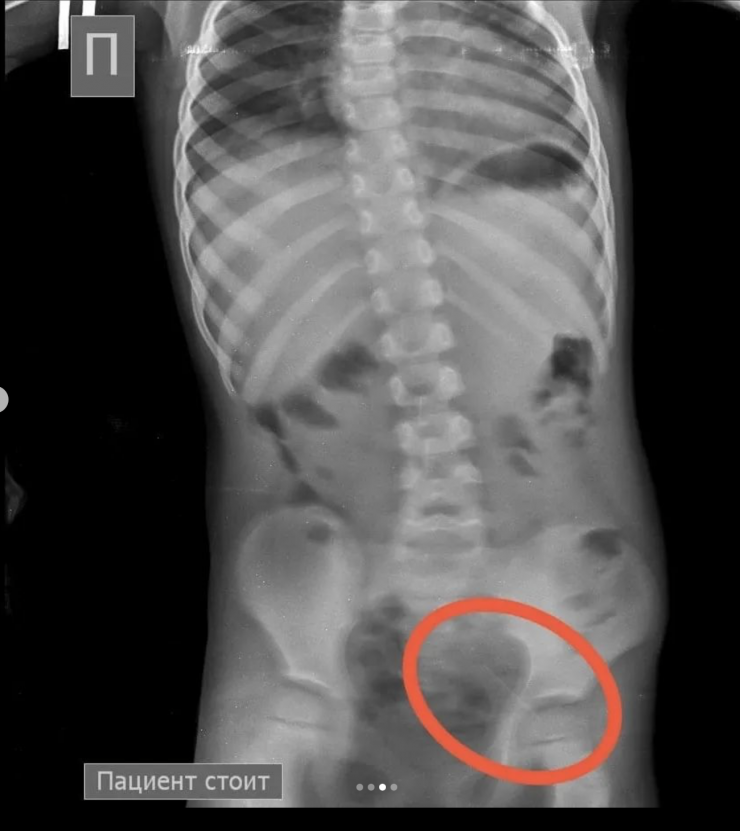

"Позже на контрольной R–грамме брюшной полости обнаружены еще две иглы в верхнем этапе брюшной полости и одна игла в проекции таза. Проведена повторная ЭФГДС, и удалена игла из желудка. Затем при помощи колоноскопии удалена игла, зафиксированная в сигмовидной кишке", - сообщил врач-хирург высшей категории Сейдахмет Чинибеков.

Однако после этого в ходе наблюдения ребенка на контрольной R–грамме брюшной полости обнаружена еще и четвертая игла в проекции таза.